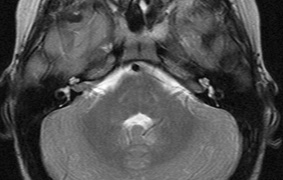

1. Schwannomas most commonly affect the fifth cranial nerve (CN), but any cranial nerve may be affected. In contrast to vestibular schwannomas (CN VIII), these typically do not grow large.84,90 Vestibular schwannomas (acoustic neuromas) are the classic finding in NF2 (Fig. 7). The risk for malignant transformation is low, but may be higher with radiation exposure.84,94

Fig. 7. Neurofibromatosis type 2: Images of a 12-year-old boy with deafness and weakness in his arms and legs, whose father has bilateral deafness. Axial T2-weighted (a) and postcontrast axial (b) T2-weighted images reveal bilateral vestibular schwannomas, which are also known as acoustic neuromas (arrows). This is the classic finding of NF2. (b, c) Bilateral schwannomas are seen in Meckel's cave (arrowheads) and a (d) lower left cranial nerve schwannoma extends into the pars nervosa of the jugular foramen (arrow). (e) A part cystic and part solid enhancing ependymoma in seen within the cervical cord and medulla and within the distal cord and conus. (e, f) Thoracic schwannomas are present at numerous levels (arrowheads). Marked enhancement and thickening of the roots within the cauda equina also represent multiple schwannomas.